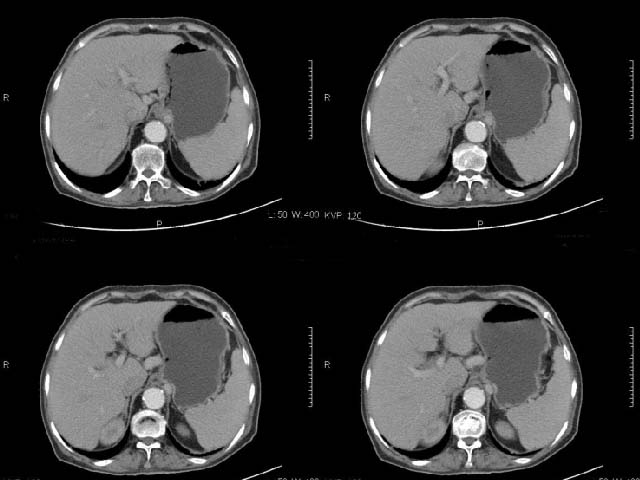

女,69岁,浑身乏力,腹泻半年余,无腹疼,排泄物中含有脂肪球,抗炎治疗一周仍不缓解,来我院检查发现明显低钾血症,给予补钾(氯化钾)一周后,血钾恢复正常,经化验检查,尿钾持续明显高于正常,临床考虑患者不仅消化道失钾,还伴有泌尿系统失钾,故进行ct增强检查看肾上腺是否有病变。ct表现为胰腺肥大,而且体尾部强化较弱,明显呈稍低密度,胰尾见有更低密度,而且胰腺与周围组织的脂肪间隙不清,大血管周围似乎有包绕现象,患者是否有过胰腺炎病史,家属说不清楚;而双侧肾上腺大小形态,本人认为未见异常,本人倾向于考虑:慢性胰腺炎伴假性囊肿,不排除胰腺占位可能;但是不知怎么解释持续尿钾现象。请大家发表高见!

动脉期